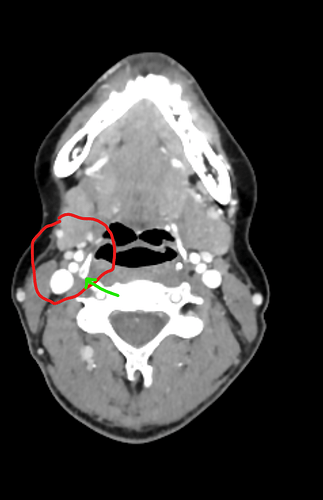

EDIT FOR CONTEXT: my CT venogram confirmed that I actually have pretty small styloids, 1 and 2 cm. But I also have “discontinuous calcification” in both stylohyoid ligaments. You can see a gap in the scan that I assume is just ligament, and then big pointy chunks of bone after that. In my personal opinion, the calcifications are angled inward quite sharply, possibly leading to more compression than someone would normally experience with calcifications this size. The right looks like it’s close enough to an artery to potentially compress it sometimes.